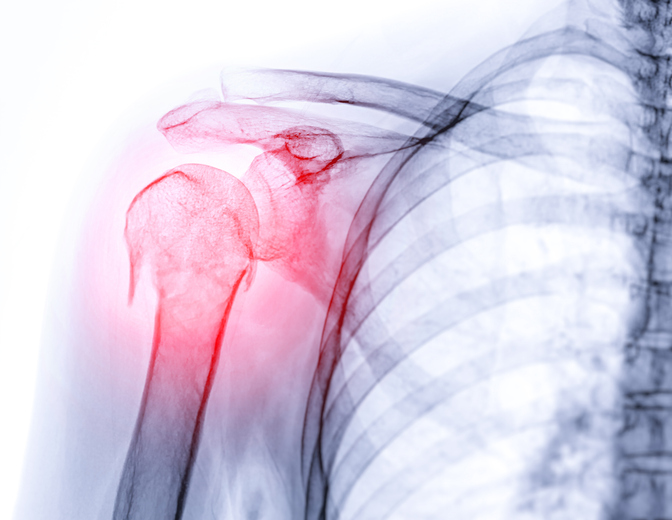

뼈 역시 마찬가지다. 뼈의 강도와 밀도는 성장기와 청년기를 거치면서 계속 증가하다가 대체로 30세 전후에 ‘최대 골량(Peak Bone Mass)’을 형성한다. 이 시기의 골량이 은행 적금처럼 노후를 지탱하는 기반이 된다. 그 이후에는 뼈의 흡수 속도가 형성 속도를 앞지르면서 골밀도가 점차 떨어진다. 특히 여성은 폐경 이후 여성호르몬 감소로 인해 급격히 뼈가 약해져 골다공증 위험이 크게 높아진다.

그러나 국내 조사 결과는 충격적이다. 2008~2010년 국민건강영양조사에 따르면 20~30대 여성의 넙다리뼈·허리뼈 골밀도는 40대 여성과 비슷하거나 오히려 더 낮았다. 젊은 시절부터 뼈 건강의 기초가 허약한 셈이다. 전문가들은 지금도 상황이 크게 다르지 않을 것으로 본다. 근육처럼 뼈도 젊을 때 최대치를 높여둬야 노후에 일정 수준을 유지하기가 수월하다.

근육이 줄면 계단 오르내리기, 장보기 같은 기본적인 생활 동작조차 어려워지고 작은 충격에도 쉽게 넘어져 골절로 이어진다. 고관절 골절을 당한 70세 이상의 노인 중 약 20%가 1년 내 사망한다는 통계도 있다.